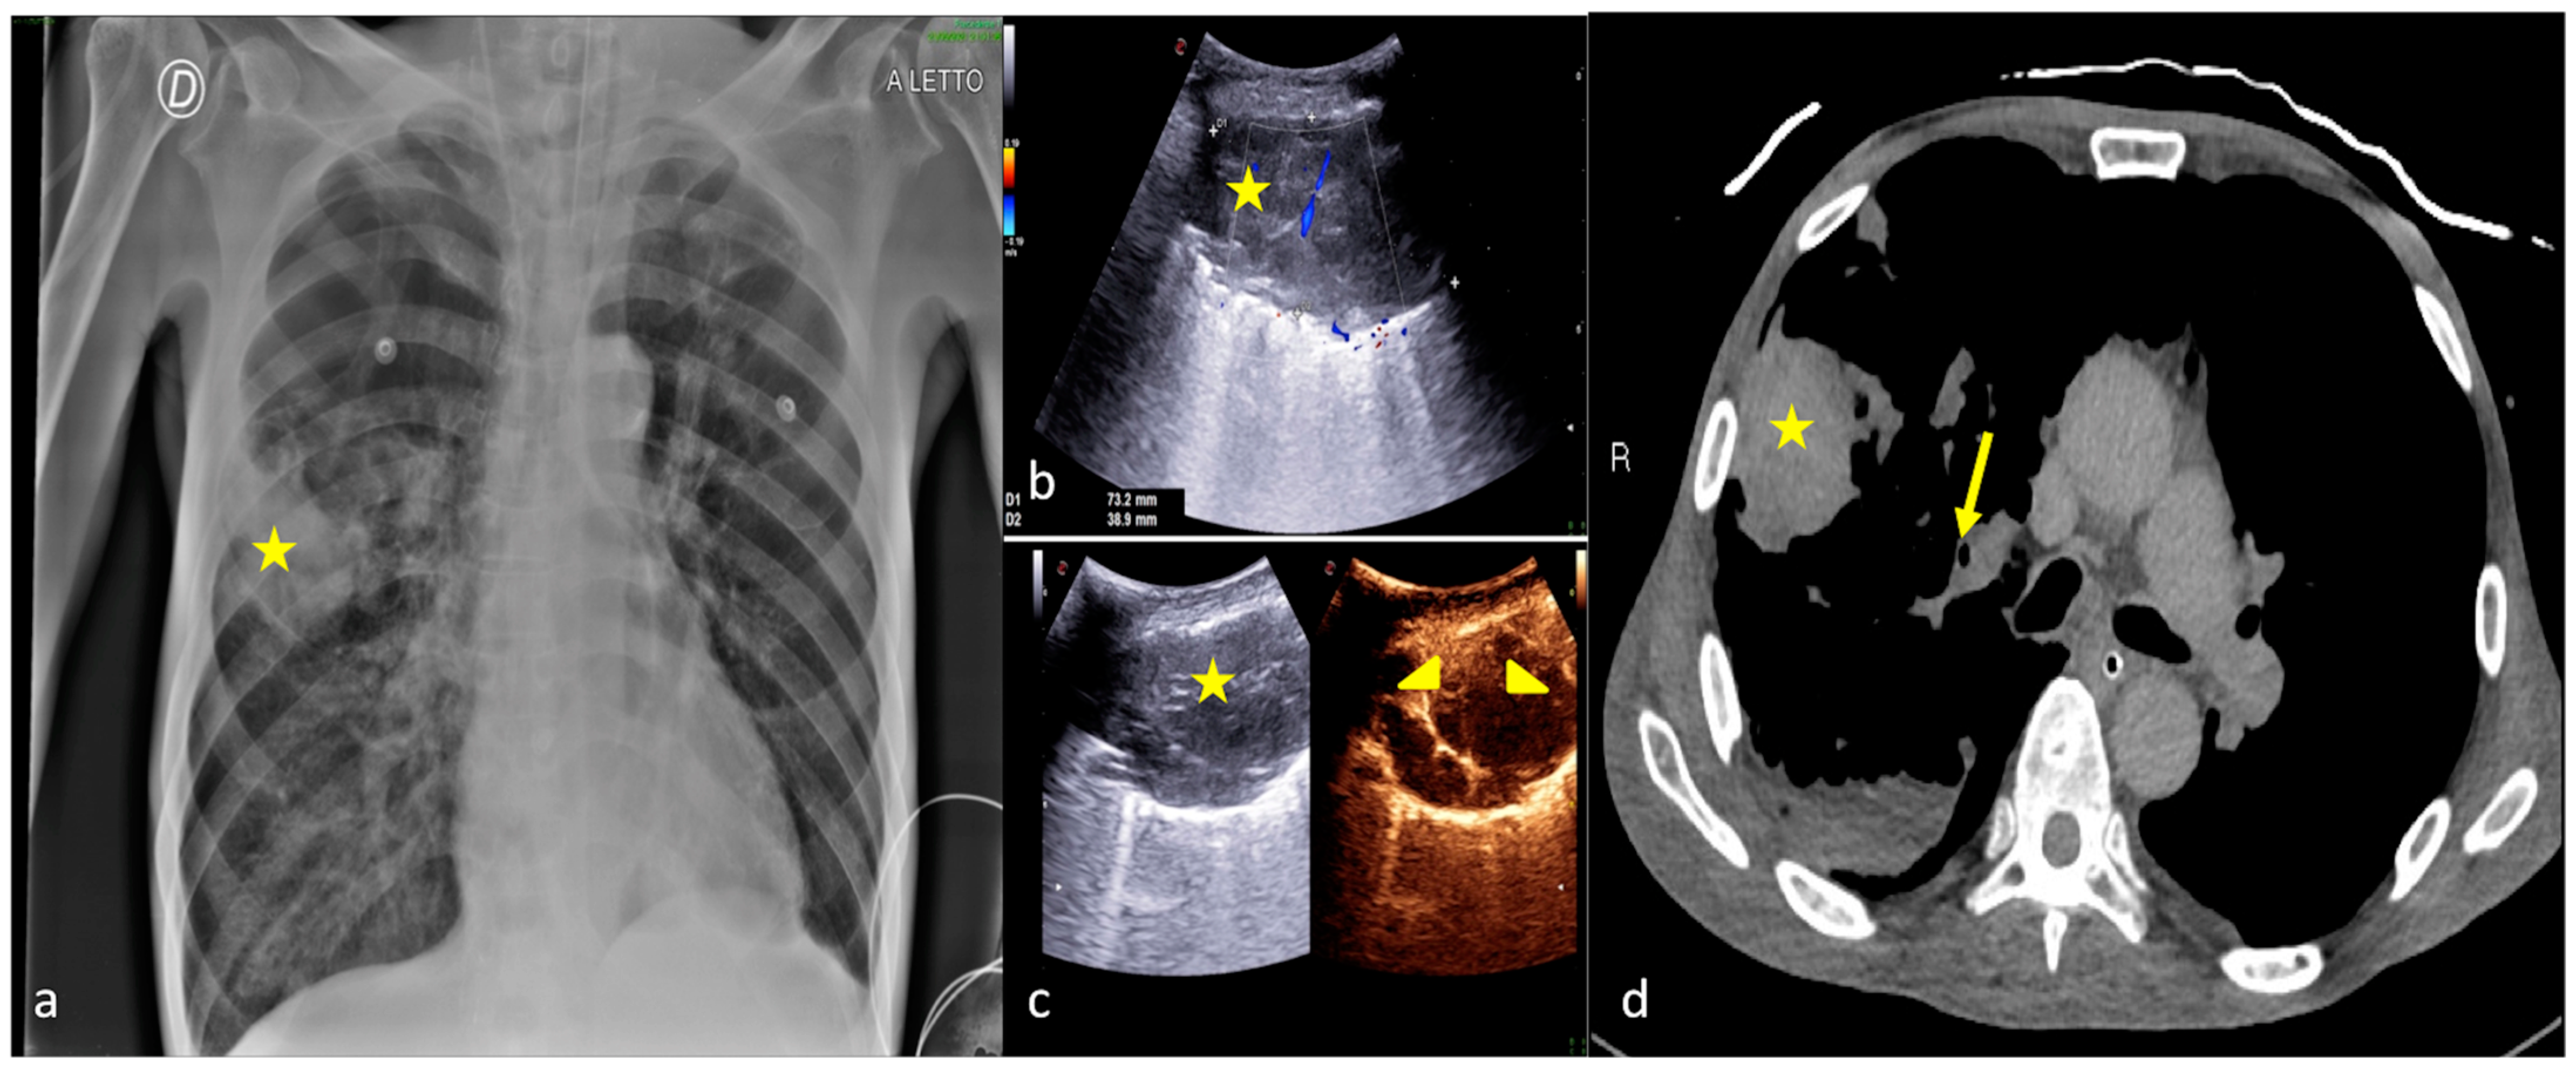

Figure 7.

A 36-year-old female patient admitted to the ICU for a comatose state related to cerebral hemorrhage with fever and dyspnea after endotracheal intubation. Bedside CXR (a) and LUS (b,c). (a) The CXR showed faint areas of decreased parenchymal transparency in the right and left inferior pulmonary field (a, arrowheads); (b). LUS confirmed the consolidative areas at the lung basis (b,c, arrowheads) with hyperechogenic spots as signs of an air bronchogram (b,c, arrows) that moved in line with the respiratory excursion. The clinical scenario and imaging findings were suggestive of phlogistic bronchopneumonia.

Figure 8.

A 26-year-old male patient admitted to the ICU for a comatose state related to high-energy trauma due to a car accident. Bedside CXR (a,c) and LUS (b). (a) The CXR on the day of admission into the ICU showed normal lung expansion with no evidence of parenchymal change. (b) LSU was performed after 24 h endotracheal intubation with the onset of a respiratory worsening and showed an inhomogeneous area of mixed hypoechogenic change at the basis of the left lung (b, arrowhead) with some hyperechogenic spots suggestive of consolidation with an air bronchogram (b, arrow). (c) The CXR confirmed the LUS findings showing an area of reduced diaphony in the basal left field that was considered the manifestation of parenchymal consolidation (c, arrowhead). The clinical scenario and imaging findings were suggestive of phlogistic bronchopneumonia.